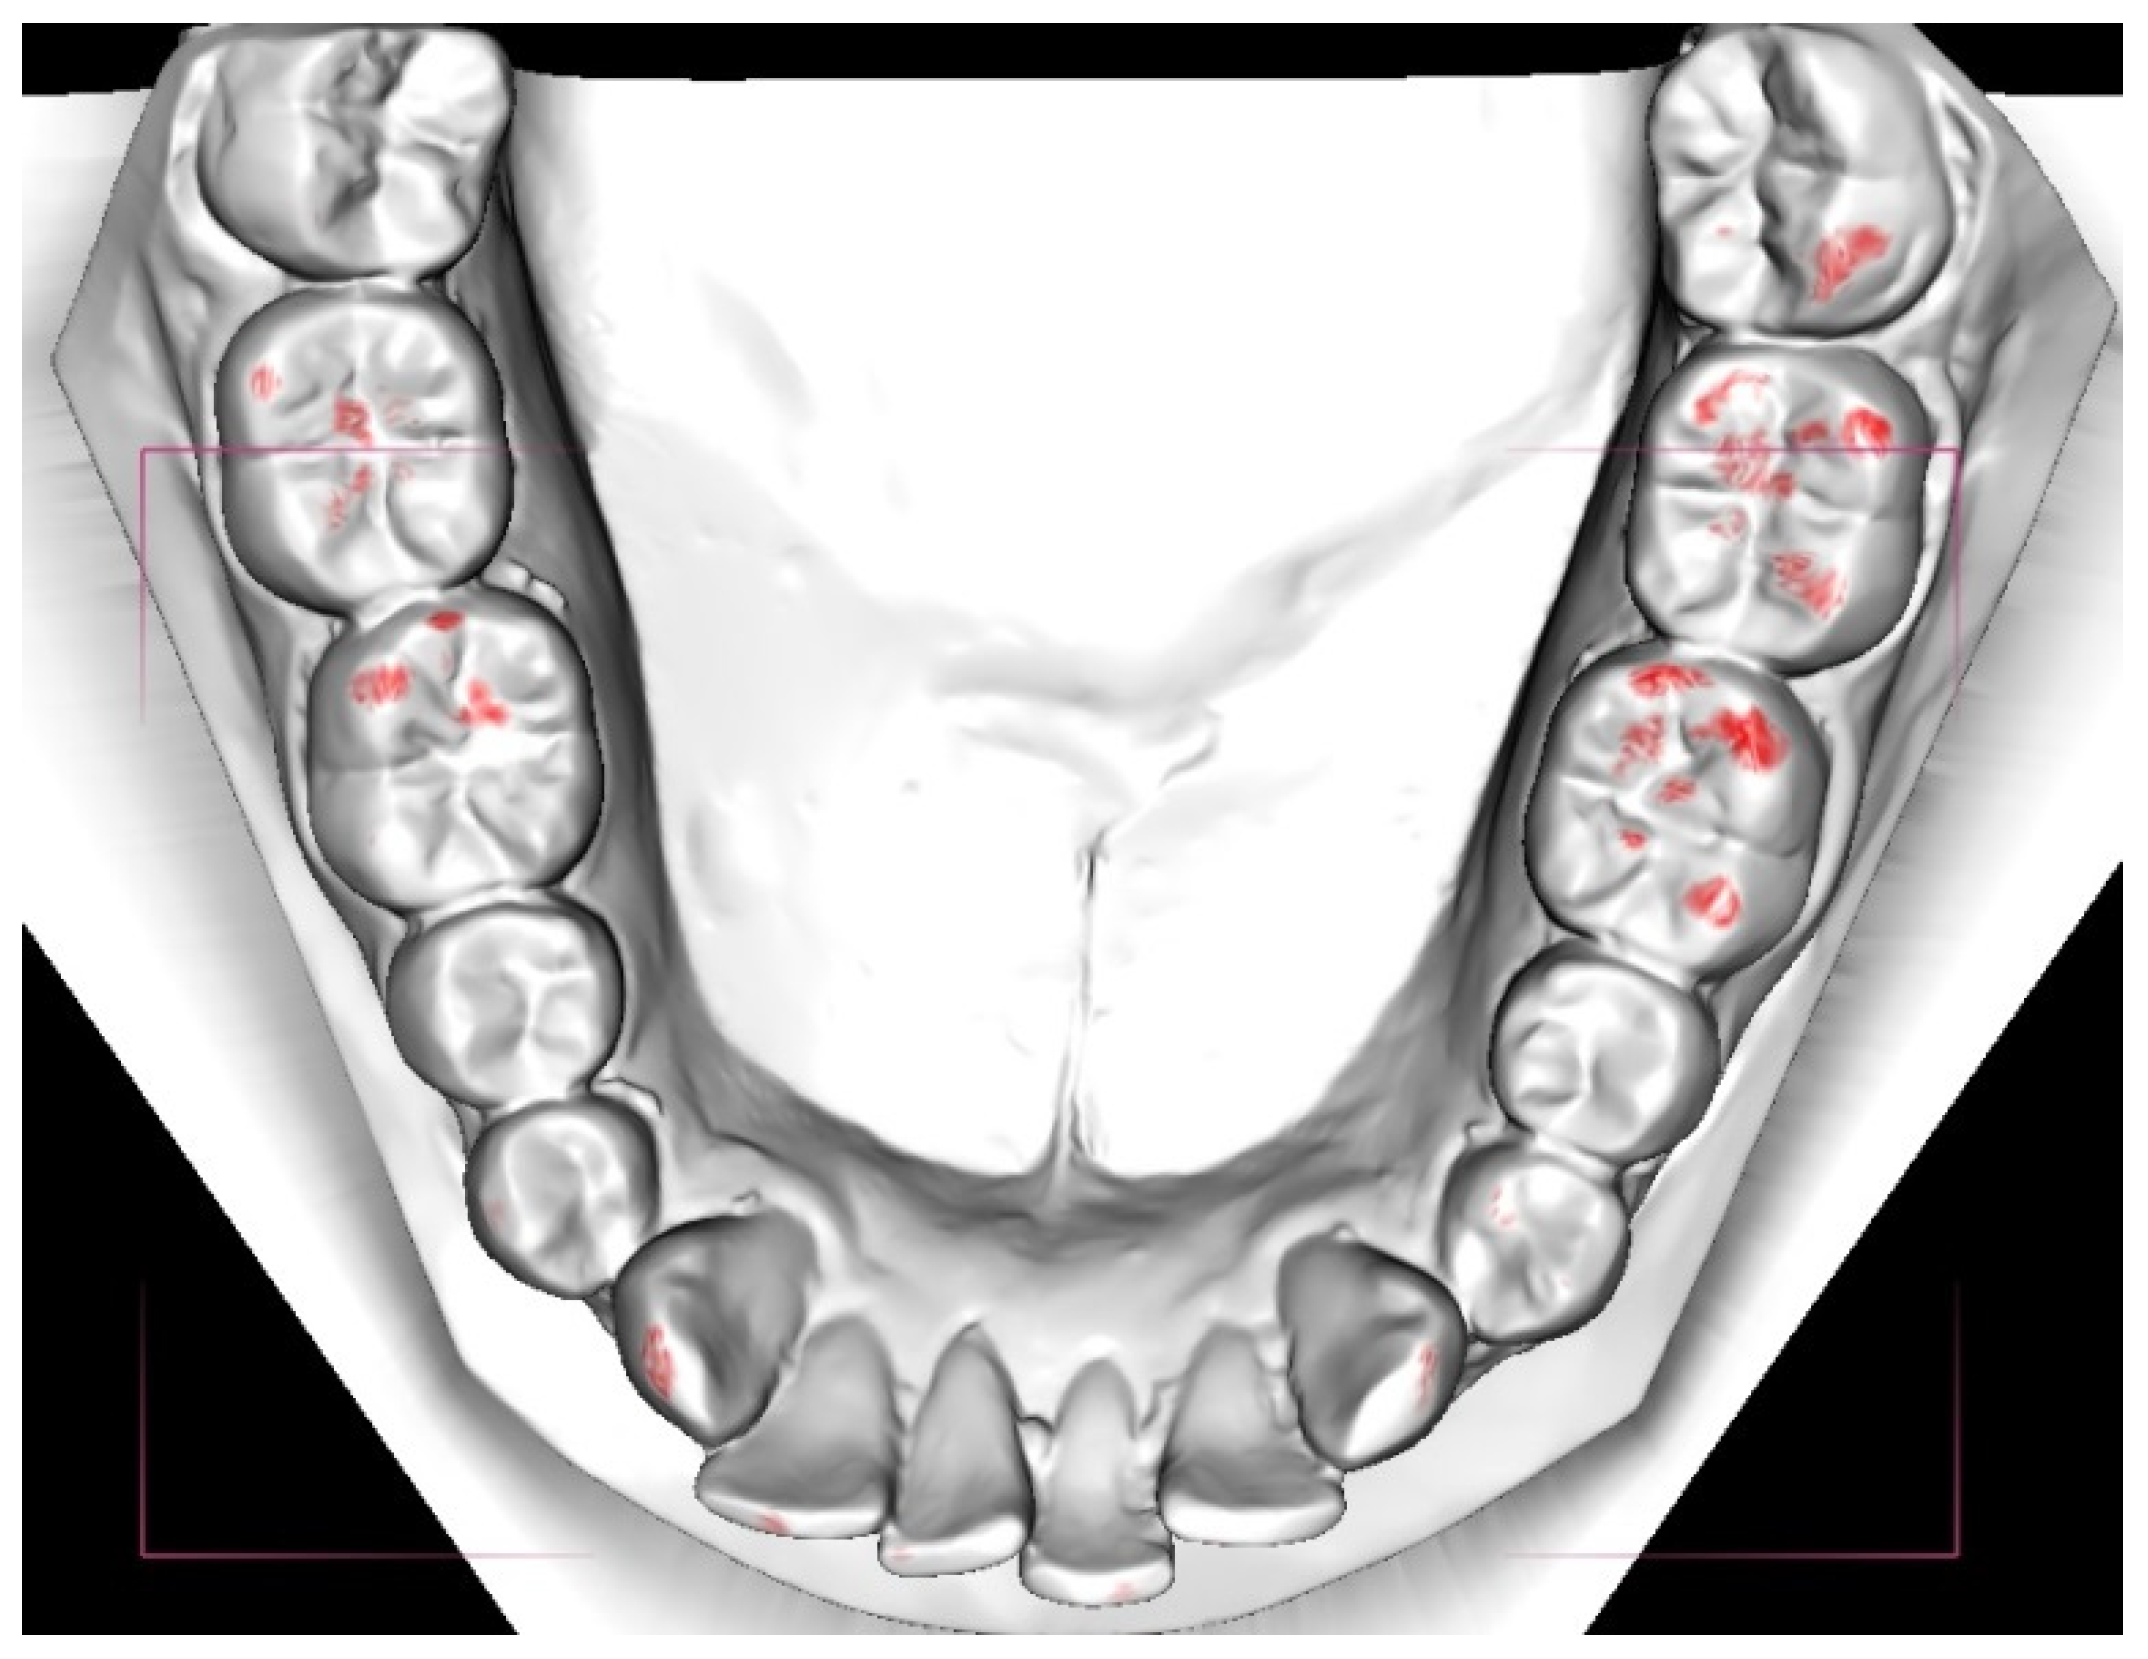

- a digital examination with the measurement of the total occlusal contact area in millimeters (DE method).

2.5. Digital Examination (DE)